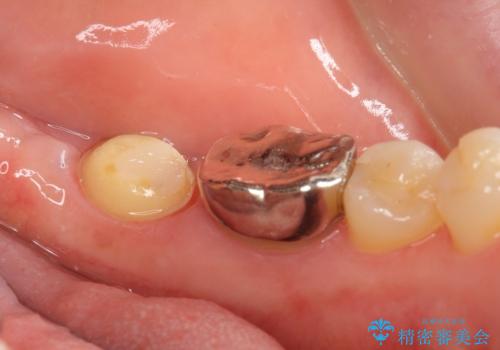

ご希望により、隣の親知らず(左下8)を移植しました。

移植後、生着を待って根管治療及び補綴修復を行いました。